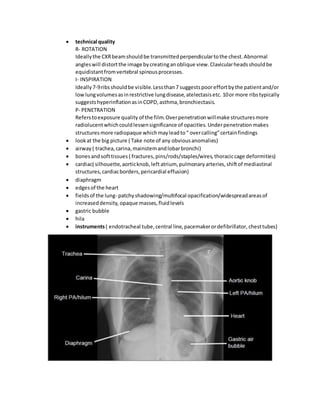

 technical quality

R- ROTATION

Ideallythe CXRbeamshouldbe transmittedperpendiculartothe chest.Abnormal

angleswill distortthe image bycreatinganoblique view.Clavicularheadsshouldbe

equidistantfromvertebral spinousprocesses.

I- INSPIRATION

Ideally7-9ribsshouldbe visible.Lessthan7 suggestspooreffortbythe patientand/or

lowlungvolumesasinrestrictive lungdisease,atelectasisetc. 10or more ribstypically

suggestshyperinflationasinCOPD,asthma,bronchiectasis.

P- PENETRATION

Referstoexposure quality of the film.Overpenetrationwillmake structuresmore

radiolucentwhichcouldlessensignificance of opacities. Underpenetration makes

structuresmore radiopaque whichmayleadto“ overcalling”certainfindings

 lookat the big picture ( Take note of any obviousanomalies)

 airway ( trachea,carina,mainstemandlobarbronchi)

 bonesandsofttissues ( fractures,pins/rods/staples/wires,thoraciccage deformities)

 cardiac( silhouette,aorticknob,left atrium, pulmonary arteries,shiftof mediastinal

structures,cardiacborders,pericardial effusion)

 diaphragm

 edgesof the heart

 fieldsof the lung- patchyshadowing/multifocal opacification/widespreadareasof

increaseddensity, opaque masses,fluidlevels

 gastric bubble

 hila

 instruments( endotracheal tube,central line,pacemakerordefibrillator, chesttubes)